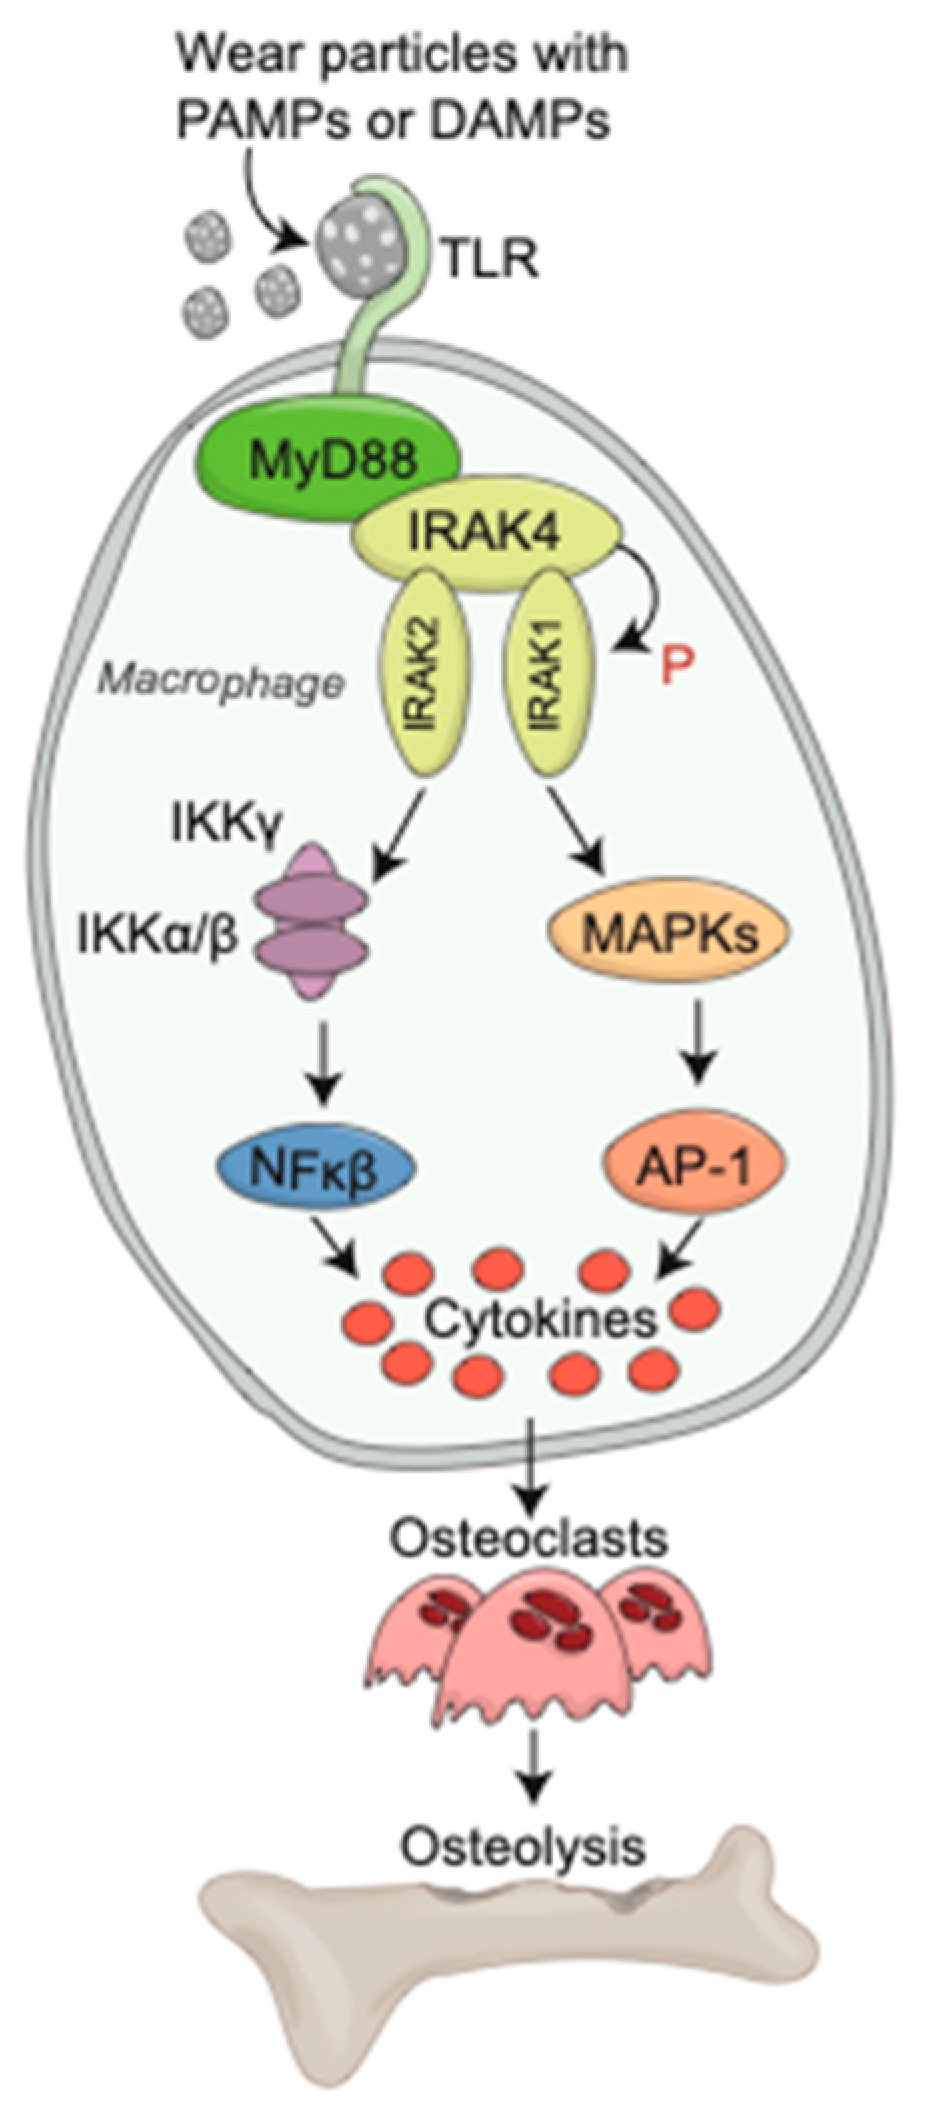

2. Innate Immune Response to Wear Debris Particles

2.1. Macrophages

2.2. Toll-like Receptors

3.1. Osteoclasts